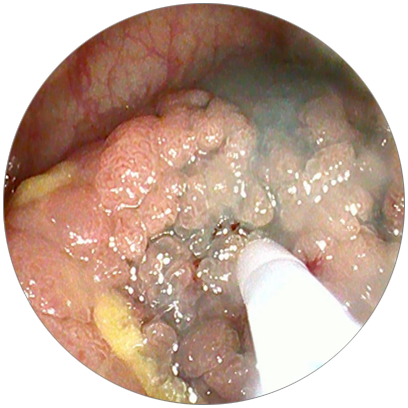

在消化內(nèi)鏡團(tuán)隊(duì)密切配合下

手術(shù)緊張有序的進(jìn)行

標(biāo)記位置

粘膜下注射

剝離

止血

經(jīng)過1個(gè)半小時(shí)的努力

手術(shù)順利完成